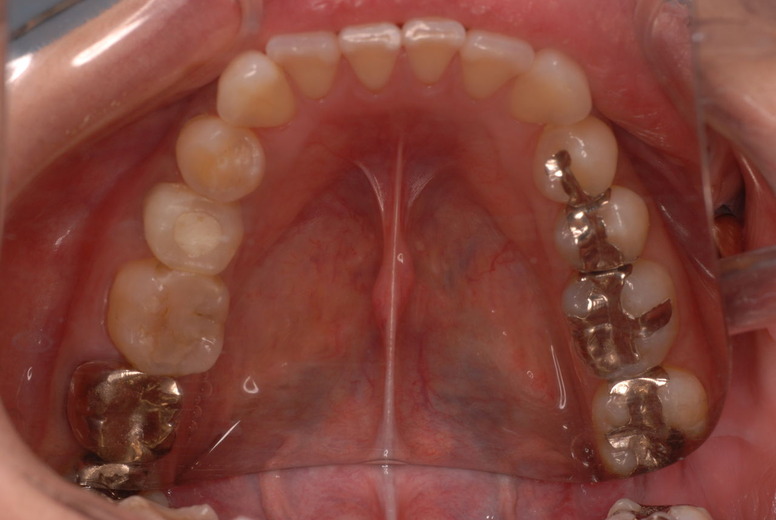

![4e36cd58-s[1]](https://livedoor.blogimg.jp/netdental/imgs/8/a/8aaefaf8.jpg)

平成24年一部欠けて来院

15年前と同じように詰めて終了。磨き方はまあまあでした。でも問題少ないでしょう。![ea7f9628-s[1]](https://livedoor.blogimg.jp/netdental/imgs/c/2/c2ef91be.jpg)

![1c81d8b6-s[2]](https://livedoor.blogimg.jp/netdental/imgs/a/4/a424b93d.jpg)

虫歯という病気を完全に治し、神経の処置で神経の病気を治し、ブラシの使い方をマスターすれば歯やお口の中は問題を起こしにくいのです。何かを被せることは注意が必要ですし、歯を傷つける訳ですからブラシの使い方をマスターしてから被せないと危ないのです。